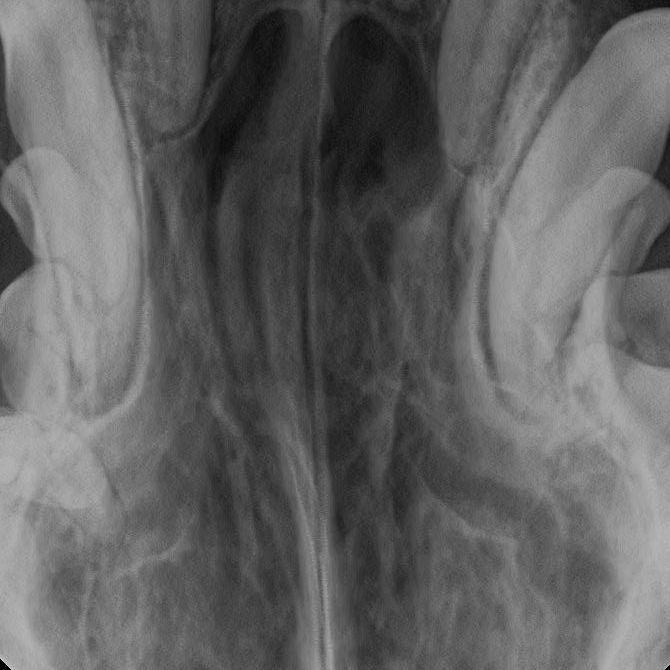

Am Tag der weiterführenden Untersuchung wurde „Prinzessin“ nach einer unauffälligen präanästhetischen Untersuchung in Allgemeinnarkose versetzt und in Narkose die Maulhöhle vollständig untersucht. Die Narkoseeinleitung erfolgte nach Prämedikation (Medetomidin und Butorphanol) mit Propofol bis zum Eintritt des Bewusstslosigkeit und wurde nach Intubation auf eine Inhalationsnarkose mit druckkontrollierter Beatmung mit einem Luft-Sauerstoff-Isofluran-Gemisch umgestellt. Zur Narkoseüberwachung wurden EKG, nichtinvasive Blutdruckmessung, Pulsoxymetrie, Kapnometrie und Thermometrie durchgeführt. Während der Narkose erhielt „Prinzessin“ Ringer-Lösung als Dauertropfinfusion über einen venösen Zugang. Als Analgetikum wurde präoperativ Metamiziol verabreicht. Nach der Eingangsuntersuchung der Maulhöhle mit Dokumentation von Zahnstein und Gingivitisindex erfolgte nach einer professionellen Zahnreinigung und Desinfektion die Sondierung aller Zähne. Hier konnten an einigen Zähnen Gingivitis Grad 1-2 erhoben werden, aber noch ohne wesentliche Beteiligung des Zahnhalteapparats. Die eingehende Untersuchung des harten Gaumens zeigte eine durchgängige Gaumenspalte von der Papilla Incisivi bis zum Gaumensegel. Dies führte dazu, dass einerseits immer wieder Futter und Trinkwasser von der Maulhöhle in die Nasenhöhle gelangen konnte und infolge aspiriert wurde. Darüber hinaus war auch der Abschluckvorgang durch das unvollständig ausgebildete Gaumensegel gestört.